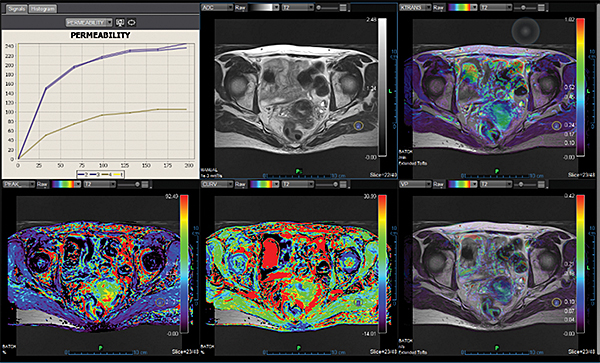

Перфузія DSC Perfusion

Додаток DSC Perfusion обчислює оптимізовані параметричні карти (rBV, rBF, TTP, MTT, TMAX, tMIP) із сирої перфузійної серії та забезпечує алгоритм для корекції ефектів розповсюдження контрастної речовини, обчислюючи карту проникності. Ця програма підтримує нерегулярний вибір часу та складається з наступних модулів: автоматична або ручна обробка arterial input function (функції артеріального наповнення), автоматична сегментація фону, чотири методи деконволюції (sSVD, cSVD, oSVD та байезівський) та алгоритм миттєвої корекції руху.

Кінетика Kinetics

Додаток Kinetics вимірює тип контрастного підсилення за допомогою аналізу кінетичних кривих і передбачає злоякісність при патологіях молочної залози та передміхурової залози.